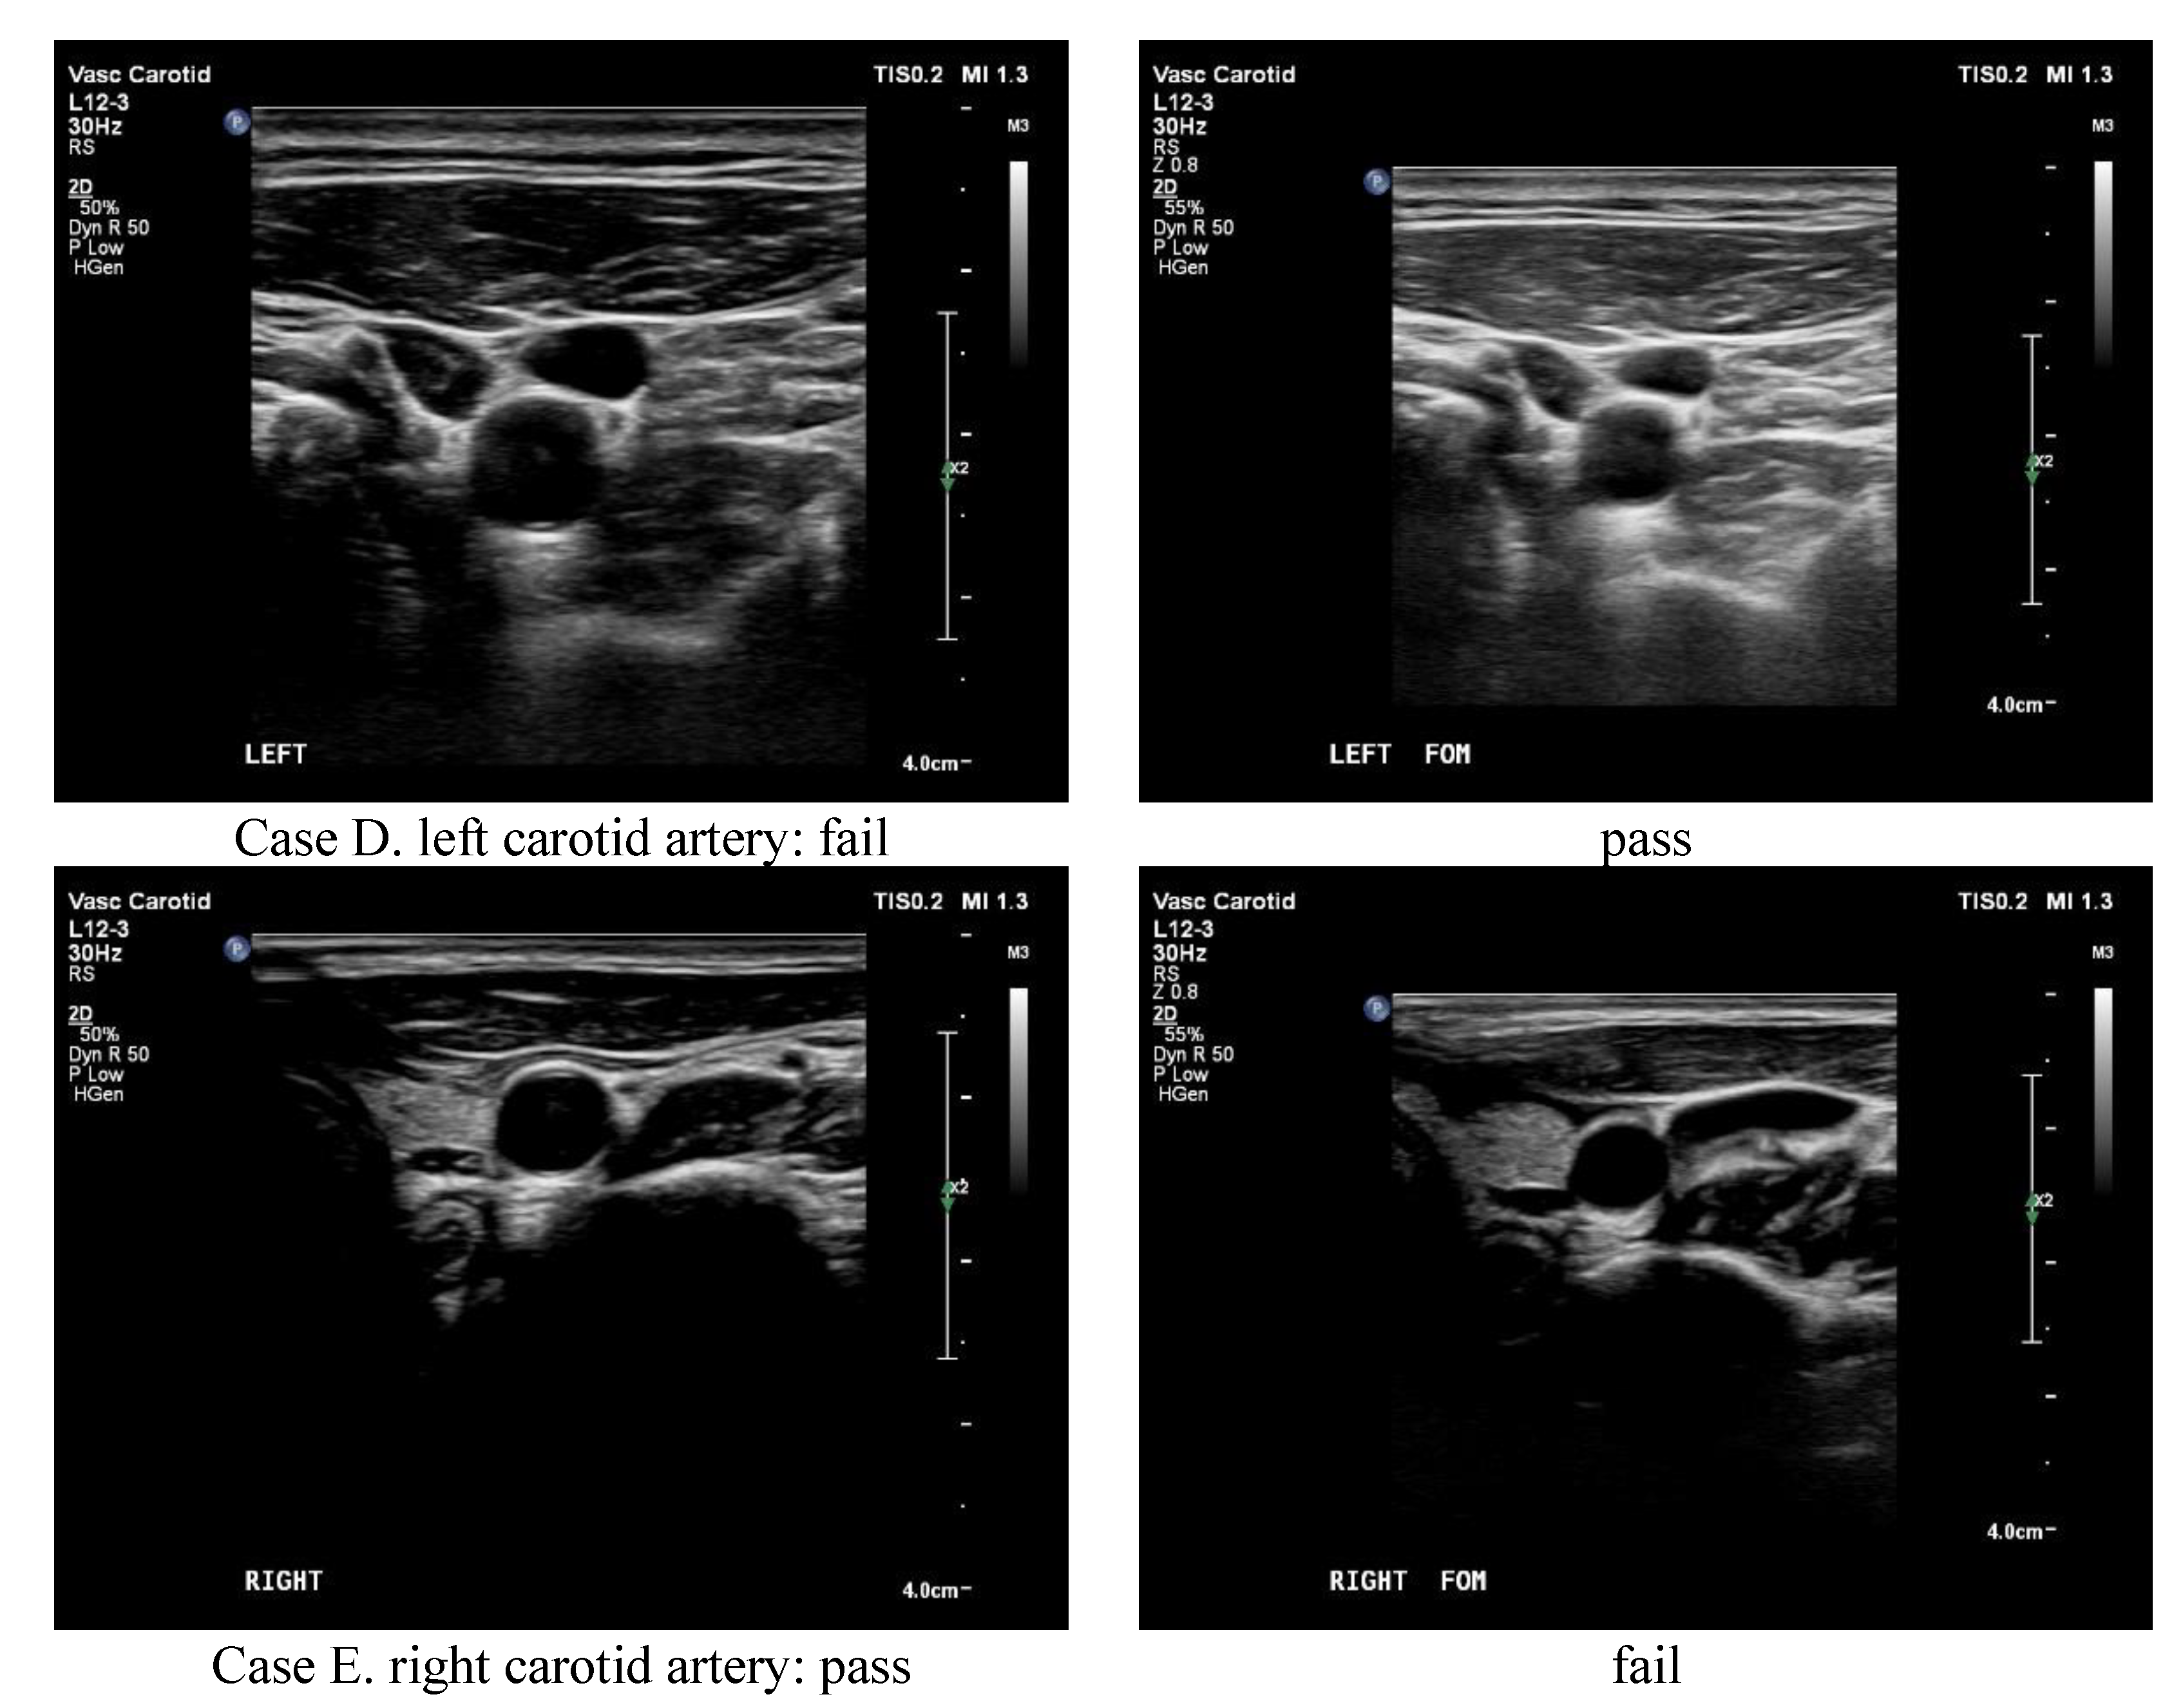

An ideal solution to solidify the Taguchi suggestion of any specific topic is either to verify or to testify in reality [13,24]. Therefore, three well-trained radiologists majoring in collecting ultrasound scan images were invited to be the reviewers of 32 pairs of scanned images taken from five volunteers on either the left or right carotid artery. Each pair of images had two corresponding images scanned from conventional or optimal settings, which were randomly submitted to the reviewers and graded as “fail” or “pass” according to their clearness and sharpness. Accordingly, the surveyed results are arranged in Table 5, and 5 out of 32 pairs of ultrasound scanned images are depicted in Figure 5. As clearly denoted in Table 5, a total of 192 images were graded (32 × 3 × 2 = 192), and the conventional combination of ultrasound preset gained 30 passes versus 66 passes for the optimal combination. Specifically, when each pair of scan slices was compared, 17 pairs of both conventional and optimal slices, 13 pairs of only optimal slices, and 2 pairs of only conventional slices passed the clinical criteria. Figure 5 also reveals the corresponding scan slices in this study. Pair A–D shows only one optimal pass, whereas pair E shows only one conventional pass that passed the clinical criteria.

Figure 5.

The ultrasound scanned images in this study. Pair (A–D) shows only one optimal pass, whereas pair (E) shows only one conventional pass that passed the clinical criteria.